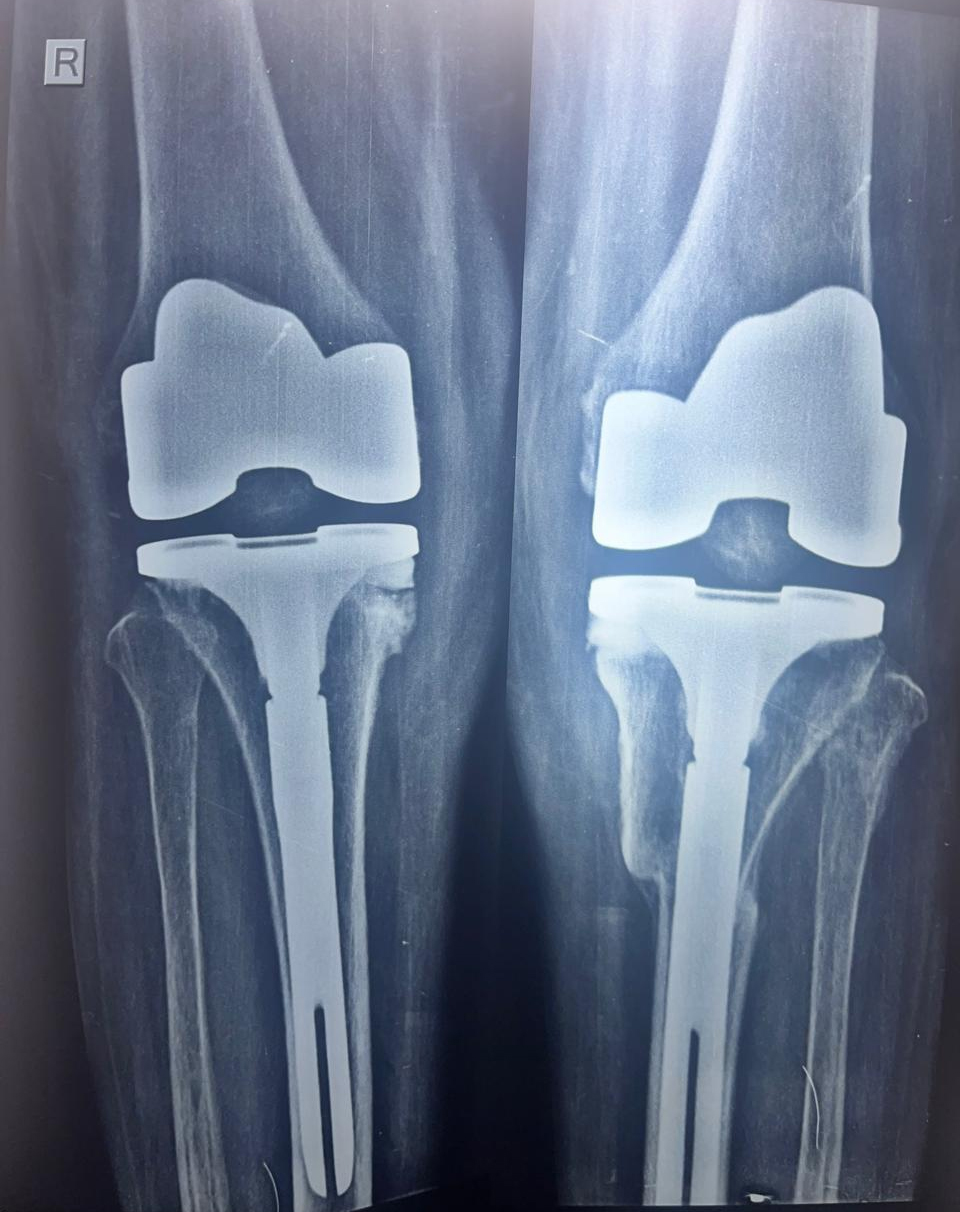

72 years female patient did not walk for 3 months suffered stress fracture of tibis on left side . Bilateral toral knee replacement done with extension rods